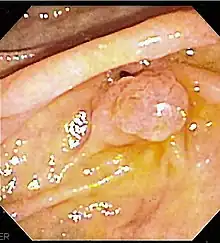

![]() The major duodenal papilla, seen on duodenoscopy at the time of ERCP. This is the protrusion of the ampulla of Vater into the duodenum. | |